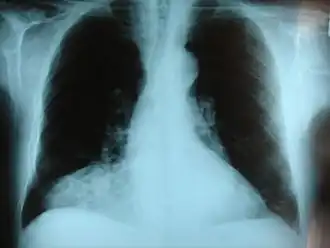

Hernie diaphragmatique congénitale